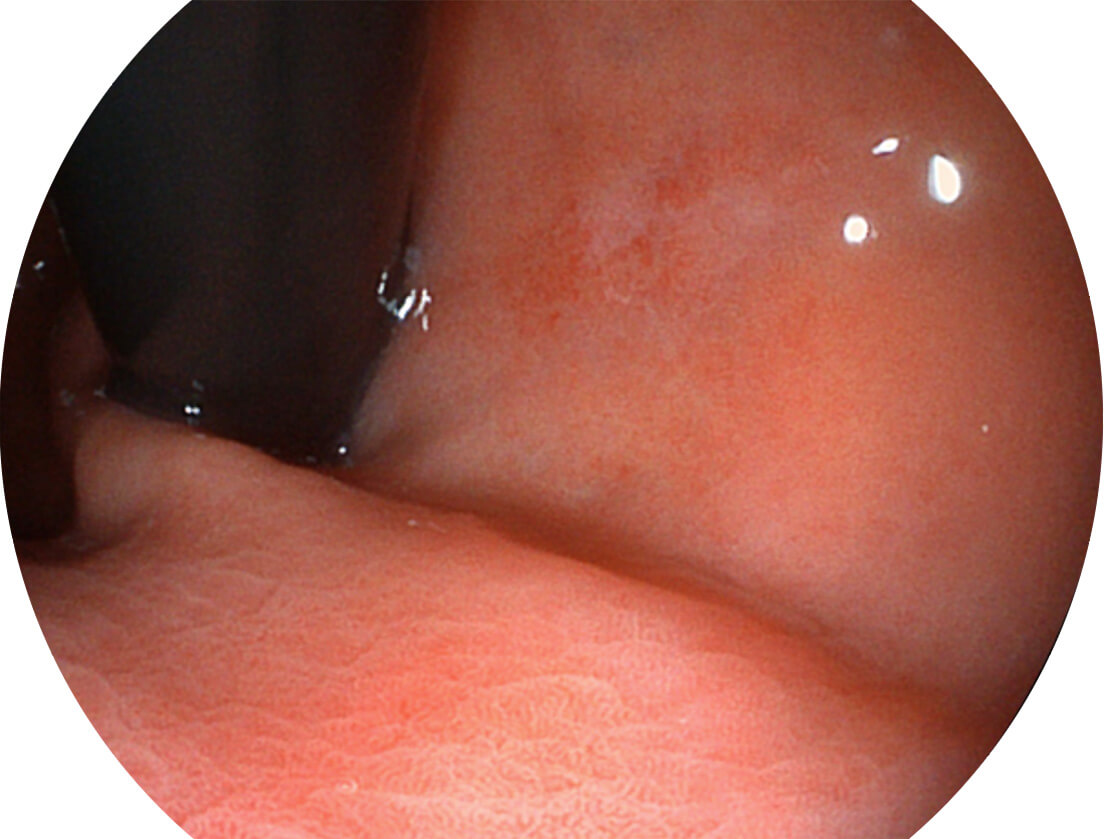

图像具有高亮度、高黏膜血管颜色对比度的特点,且不改变粘液、食物残渣、粪便的基本颜色,可在中远景下进行观察,助力消化道早期疾病的诊断。

SFI图像